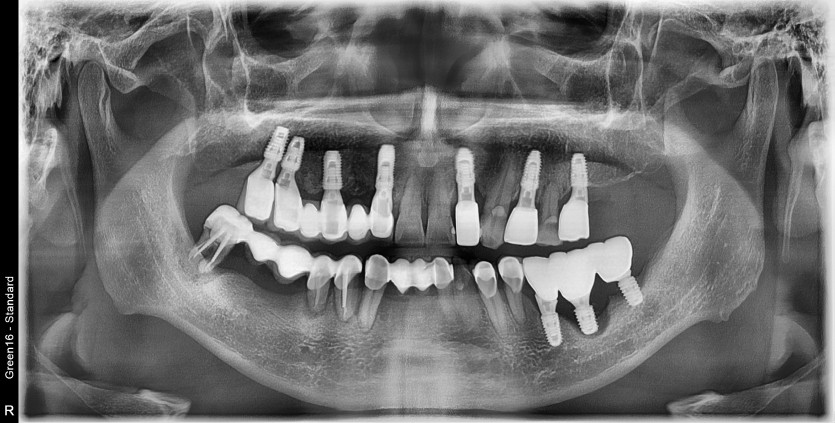

30번대 임플란트 재수술